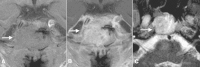

Metastatic disease to the clivus mimicking clival chordomas

Objectives/Hypothesis A comprehensive review of the literature of clival metastases and presentation of two additional cases. Study Design Literature review and report of two cases. Methods A literature review of the MEDLINE database (1950 to January 19, 2013) was performed to identify all cases of patients with metastatic disease to the clivus. Additionally, two novel cases are presented. Results In total, 47 cases were identified in the literature, including the two cases presented in this study. Metastatic disease to the clivus is the initial presenting symptom of the primary malignancy in 36% (13/36) of the cases. When there was a history of malignancy, the median interval of time to clival metastases was 24 months (range 1 to 172 months). Clinical symptoms manifested often as cranial neuropathies, with at least abducens palsies as the initial presenting symptom in 61.9% (26/42) of patients. Tumor pathology was diverse, but several pathologies were seen more commonly: prostate carcinoma (18.1%, 9/47), hepatocellular carcinoma (10.6%, 5/47), and thyroid follicular carcinoma (8.5%, 4/47). Conclusion Although clival metastases are extremely rare, they are an important part of the differential of clival masses as they can be the presenting symptom of distant malignancy. Level of Evidence 4.